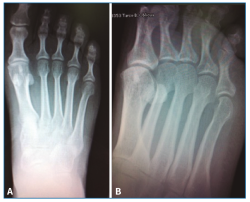

Se solicitó una resonancia magnética (RM) en dispositivo convencional de 1,5 T que no objetivó patología neurológica intermetatarsiana, pero en la que se observaba una alteración de señal localizada en la diáfisis-epífisis distal del cuarto metatarsiano, hipointensa en T1 e hiperintensa en T2, compatible con edema óseo, y que se informó como fractura de estrés (Figura 2).

Figura 2. Resonancia magnética en corte coronal (A) y axial (B) que muestra una alteración de señal hiperintensa en T2 a nivel diáfisis-epífisis del 4.º metatarsiano.